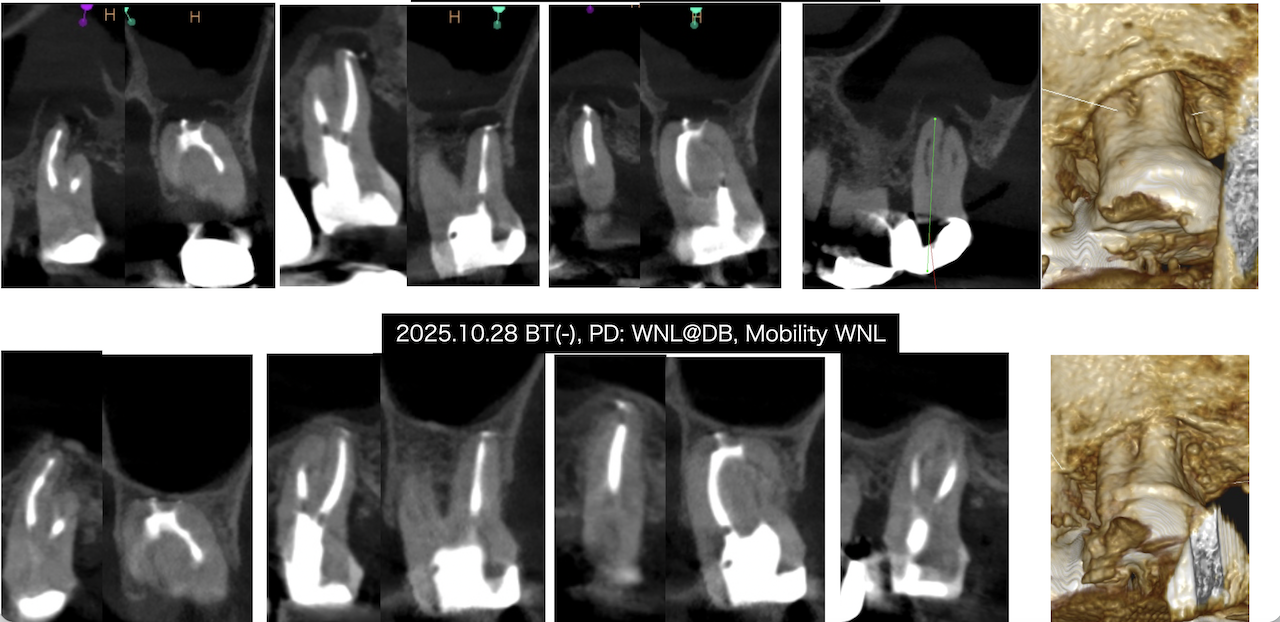

Pre-op Endo Test(2024.7.31)

PA(2024.7.31)

CBCT(2024.7.31)

MB

DB

P

根尖病変があり、上顎洞炎を呈している。

根管治療が必要だ。

Pre-op Endo Diagnosis(2024.7.31)

Pulp Dx: Pulp Necrosis

Periapical Dx: Symptomatic apical periodontitis

Recommended Tx: RCT